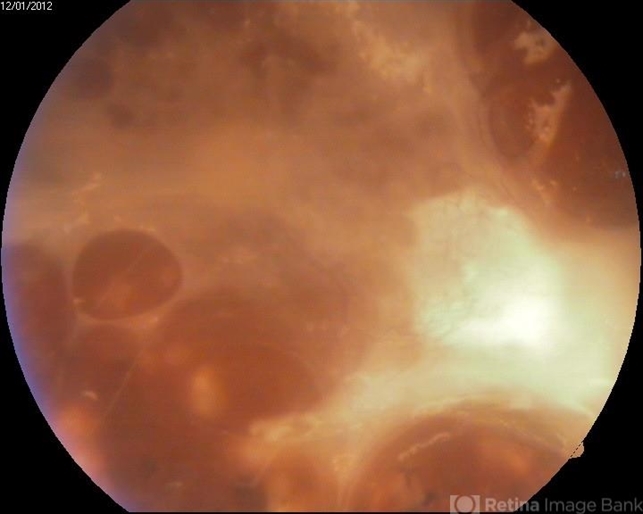

- Proliferative Diabetic Retinopathy

- neovascularization (NV)

- Color fundus photography of a 62- year-old diabetic patient. Severe fibrous proliferations with traction retinal detachment can be seen. Pars plana vitrectomy was preformed on that eye.